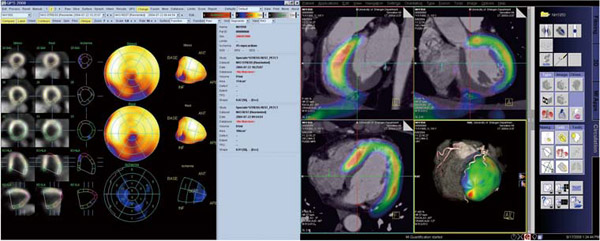

上品なファッション 新核医学技術総論臨床編 | Amazon | 通販 | |本 日本核医学技術学会 健康・医学の詳細情報

新核医学技術総論臨床編 | 日本核医学技術学会 |本 | 通販 | Amazon。日本核医学技術学会。心臓核医学の最新技術情報 - 技術解説 - シーメンス・ジャパン。茨城産10kg 精米 新米 コシヒカリ。購入時のコメントしないで下さいm(__)m随時価格を見直しておりますので値下げのお問合せはご遠慮下さいm(__)m大事なご連絡の見逃し防止のためお問い合わせ以外のメッセージ(挨拶、お礼、入金連絡等)はお控え下さいm(__)m\r\r【状態】\rカバーに使用感が少しありますが、中の紙面は良好な状態です。。骨形成因子4(切断型)(BMP-4), ヒト, 組換え体・Bone。\r\r【発送方法】\r基本1日おきに発送してますので最短お支払い当日、最長2日後発送です。循環器ジャーナル 6冊セット まとめ売り 医学書院 2017年 2018年 医学